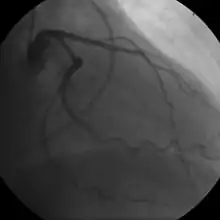

Coronary angiogram of a male

For symptomatic people, stress echocardiography can be used to make a diagnosis for obstructive coronary artery disease.[68] The use of echocardiography, stress cardiac imaging, and/or advanced non-invasive imaging is not recommended on individuals who are exhibiting no symptoms and are otherwise at low risk for developing coronary disease.[68][69]